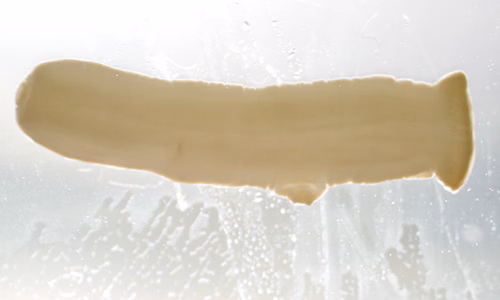

The DPDx Team received a pair of proglottids from a state health lab for cestode confirmation and identification. The specimens were submitted in 70% ethanol and measured on average 12.0 mm long by 3.0 mm wide. The proglottids were reportedly found in the feces of a 43-year-old woman with no documented international travel. Figures A and B show one of the proglottids. Figures C and D show the same proglottid after soaking in lactophenol for several hours. What is your diagnosis? Based on what criteria?

Figure A